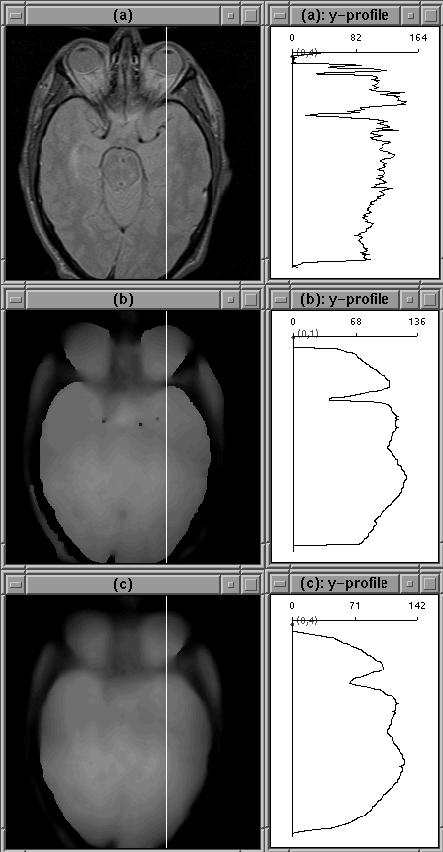

The 1D experiments are encouraging, but inconclusive. In some cases, filtering isolates the intracranial boundary, in others it does not. The image slice from the previous experiment was then filtered using the 2D filter. The results are shown in Figure 4.12 for 2 sets of filter parameters. Although the intensity of tissues outside the brain has been decreased, a simple threshold is unlikely to remove all those tissues. Still the intensity reduction is likely to simplify an intensity-based segmentation approach.

Figure 4.12: Images after 100 iterations of 2D diffusion. (a) Original Image. (b) Diffused image, . (c) Diffused image, . The filter has not attenuated the eye tissue as desired.

The image cross-sections shown in 4.12 show that a reasonable profile of RF inhomogeneity was not produced by the diffusion process. The filter parameters cannot be adjusted so that the filter simultaneously attenuates non-brain regions, tracks the edge of the brain, and profiles RF inhomogeneity.